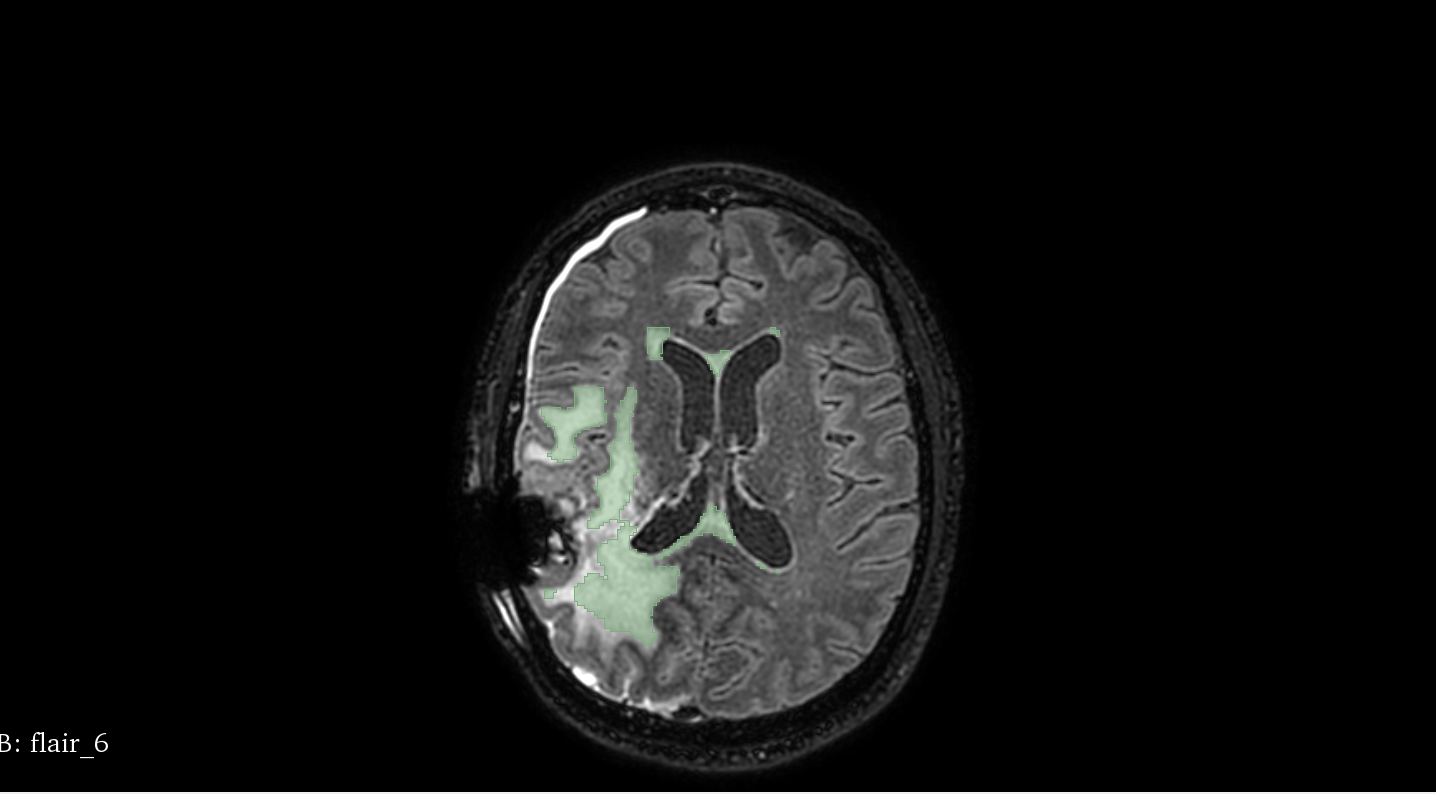

• Image FLAIR - Avec le crane

• prob - probabilité / carte (presque) entre 0 et 1 à l'emplacement des WMH

• segm - segmentation

Patient 58